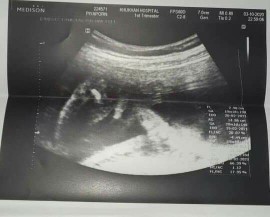

มาอวดภาพอัลตร้าซาวด์กันหน่อยแม่จ๋า 🤰🏻👼🏻 ชาย หรือ หญิง กันนะ?

โพสใต้คอมเมนต์กันได้เลยนะแม่ ♥️ แอดอยากเห็นๆ 7/11/2563